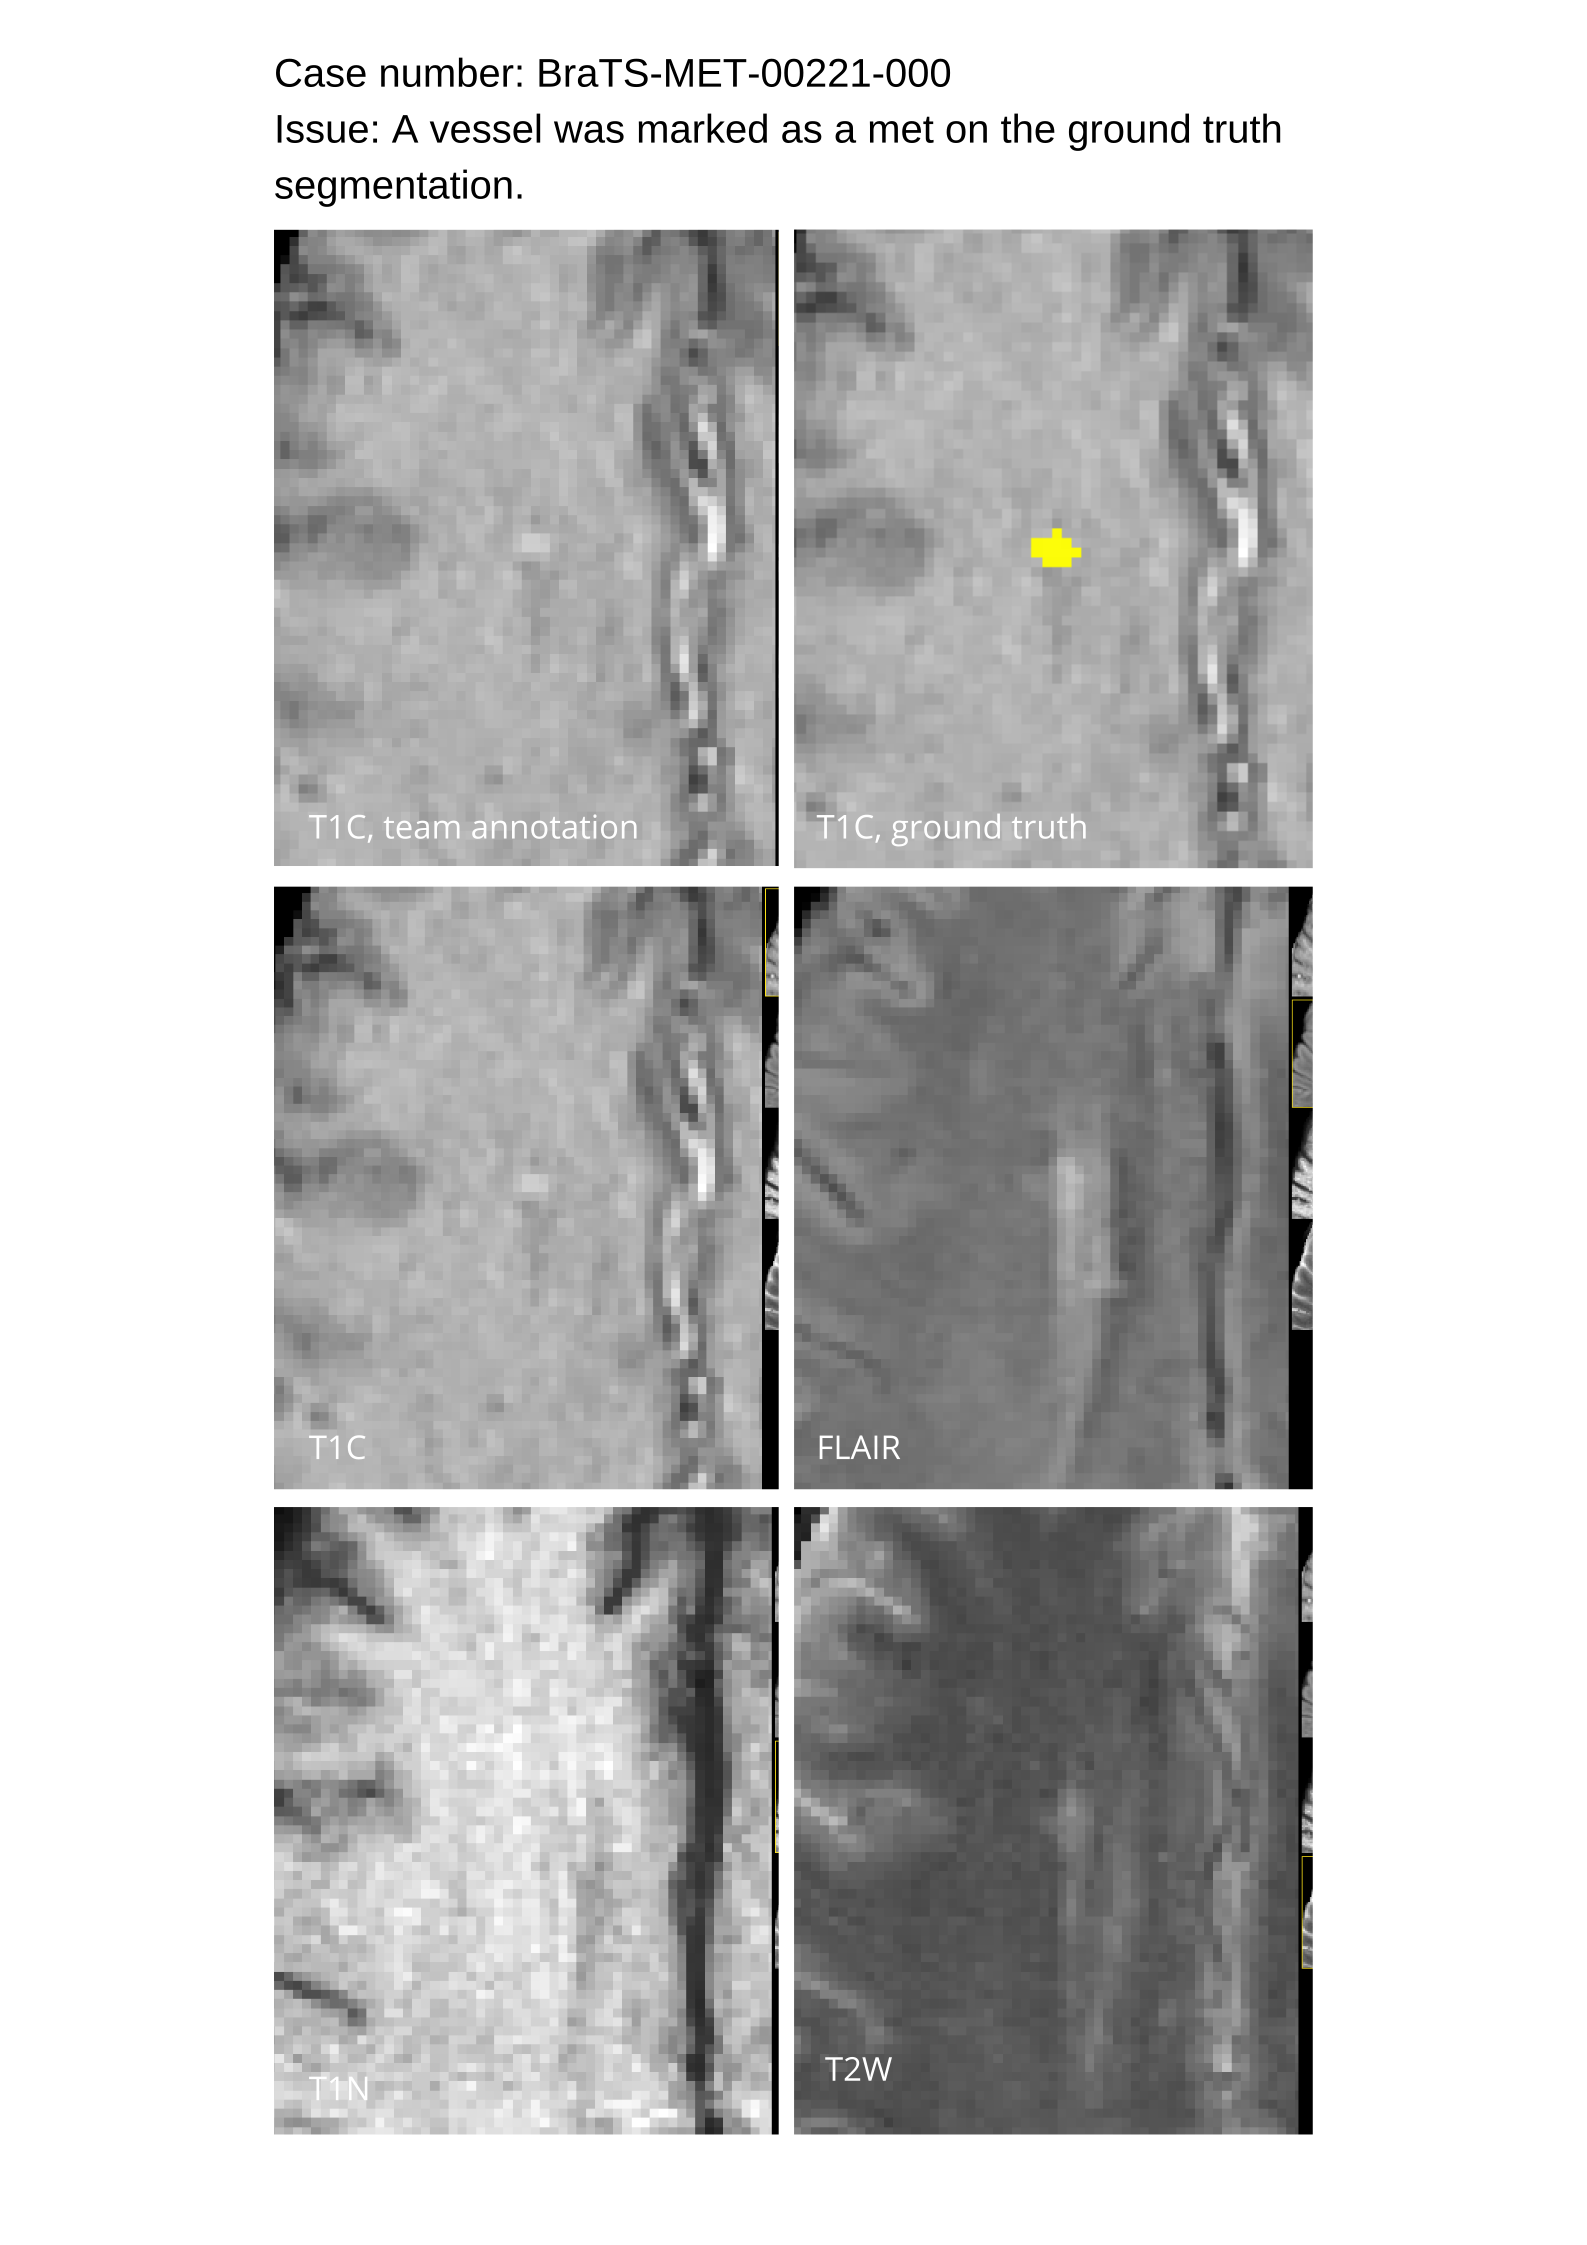

4.9 Common Errors of Automated Segmentations

Based on observations from previous BraTS challenges, common errors in automated segmentations were identified. The most typical errors in the current challenge included:

1. 1.

Automated algorithms missing small metastases. Enhancing metastasis was fused using the minority voting algorithm to aggregate all enhancing tumor voxels identified by the three algorithms. However, many small metastases were missed and were manually segmented by neuroradiology attendings.

2. 2.

Segmentation of white matter changes from microvascular disease. Peritumoral edema segmentations were checked by neuroradiology attendings and modified.

3. 3.

The segmentation of non-enhancing lesions that have intrinsic T1 hyperintensity. Voxels with intrinsic T1 hyperintensity were manually removed from ET segmentations.

These insights led to specific adjustments in the annotation process to enhance accuracy.